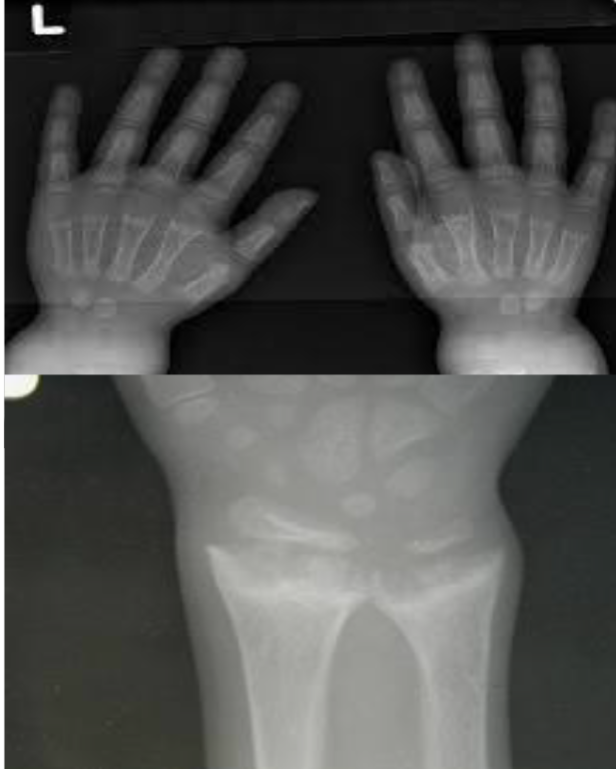

What are the clinical findings? 23-month-old with bowing legs, not growing properly, and exclusively breastfed until 11 months.

What are the X-ray findings? Widening, cupping, and fraying of metaphyseal regions, osteopenia, and widened and irregular epiphyseal plates.